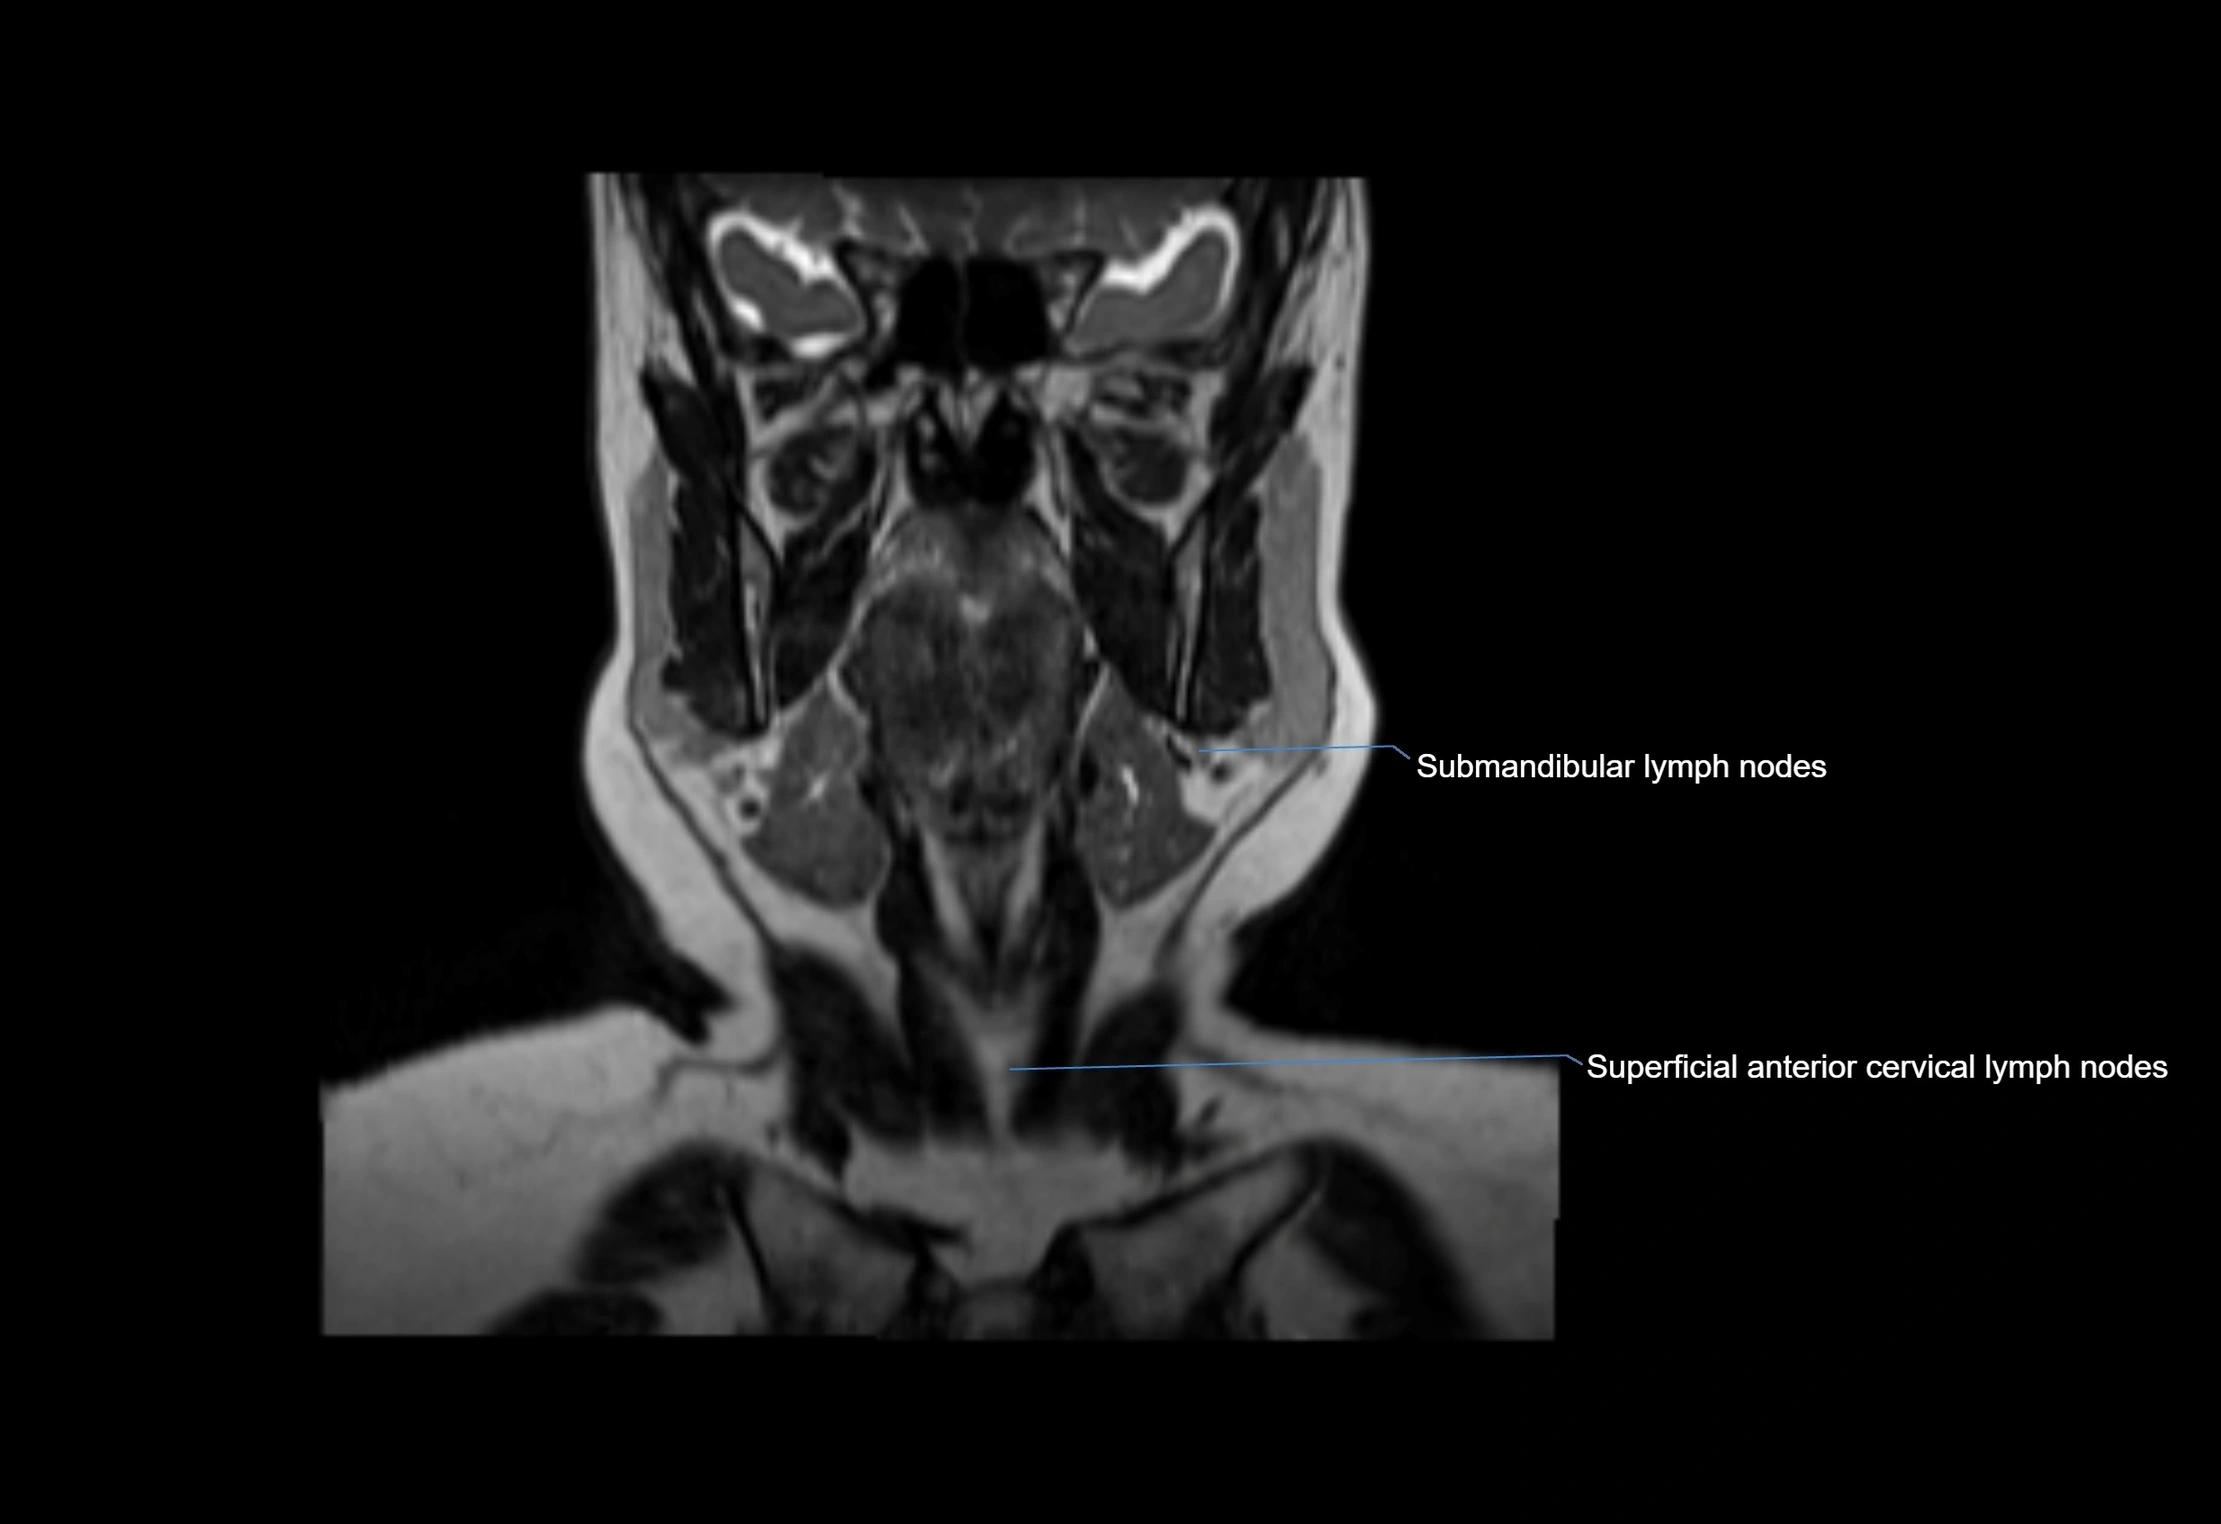

MRI Appearance

T1-weighted images:

• Normal accessory nodes appear as small, oval hypointense to intermediate signal structures within subcutaneous fat

• Surrounded by hyperintense fat, enhancing contrast for visualization

• Pathological nodes may appear enlarged or rounded, sometimes with cortical thickening

T2-weighted images:

• Nodes show intermediate signal, with surrounding fat bright

• Useful for detecting edema, inflammation, or infiltration

• Fatty hilum may appear slightly hyperintense relative to cortex

MRI images